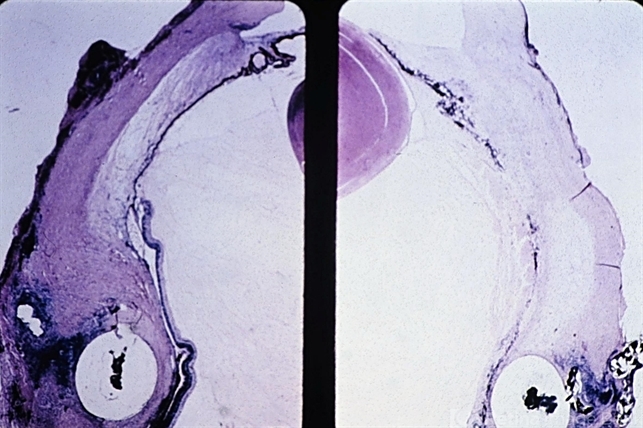

- retinal necrosis, ciliary

- Ischemic necrosis of iris and ciliary body (right) in eye following scleral buckling procedure with the use of a polyethylene tube.